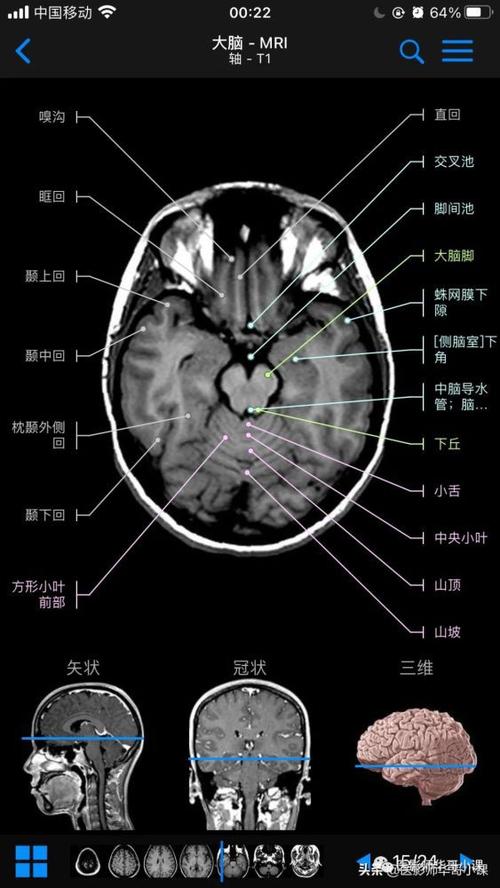

高清mri图颅脑磁共振mri解剖

颅脑磁共振解剖图谱